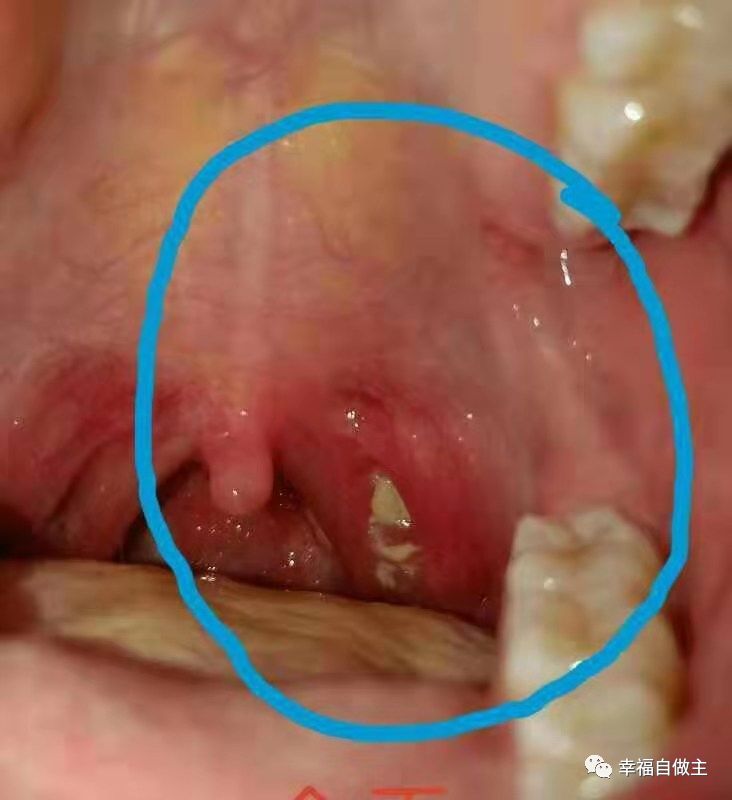

按推第一天

按推第二天

按推第三天

按推第四天